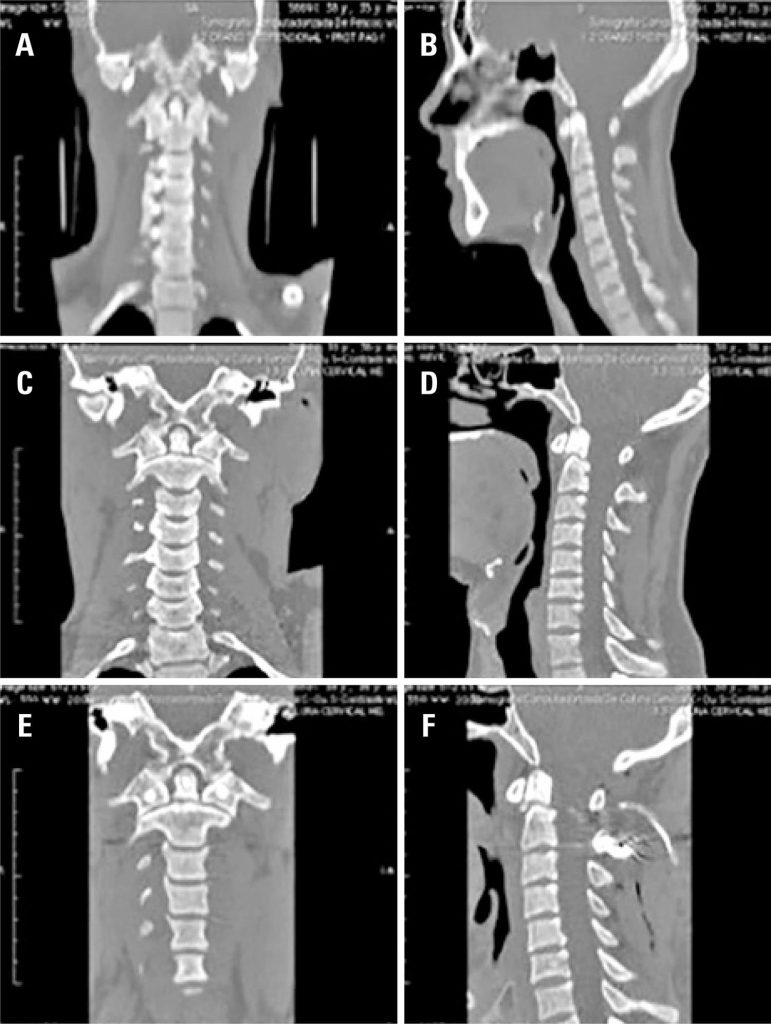

Análise retrospectiva de série de casos com lesões traumáticas da junção craniocervical

Foram analisados 37 pacientes, 73% eram do sexo masculino e a média de idade foi de 41,7 anos. Inicialmente 32% dos pacientes foram submetidos a tratamento cirúrgico, e 68% foram submetidos a tratamento conservador. Sete pacientes (29%) do grupo conservador foram submetidos posteriormente à cirurgia. No grupo cirúrgico, houve sete casos de fratura de odontóide tipo II, dois casos de fratura de elementos posteriores do áxis, um caso de luxação C1-C2, um caso de deslocamento occipito-cervical e um caso de fraturas de C1 e C2 e luxação facetária. Um paciente apresentava déficit neurológico, melhorando após o tratamento. Houve duas complicações pós-cirúrgicas, uma fístula liquórica e uma infecção de ferida operatória (reabordada). No grupo conservador, predominaram as fraturas do odontóide (oito) e dos elementos posteriores de C2 (cinco). Em dois casos, havia também fraturas em outros segmentos da coluna. Nenhum dos pacientes deste grupo apresentou deterioração neurológica.

As lesões da junção craniocervical são raras, sendo mais frequentes as fraturas do odontóide e dos elementos posteriores do áxis. Nossos resultados recomendam o tratamento cirúrgico precoce para os pacientes com fraturas do odontóide tipo II e lesões ligamentares, e tratamento conservador para os demais pacientes.